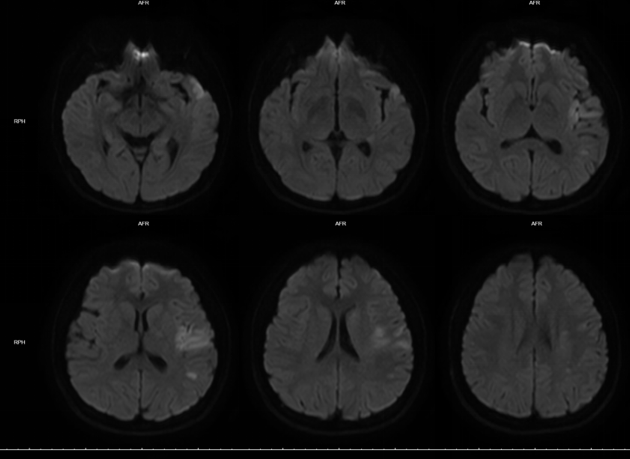

MRI:左侧大脑半球多发急性脑梗死灶。

MRA:左侧大脑中动脉闭塞。左侧颈内动脉狭窄。